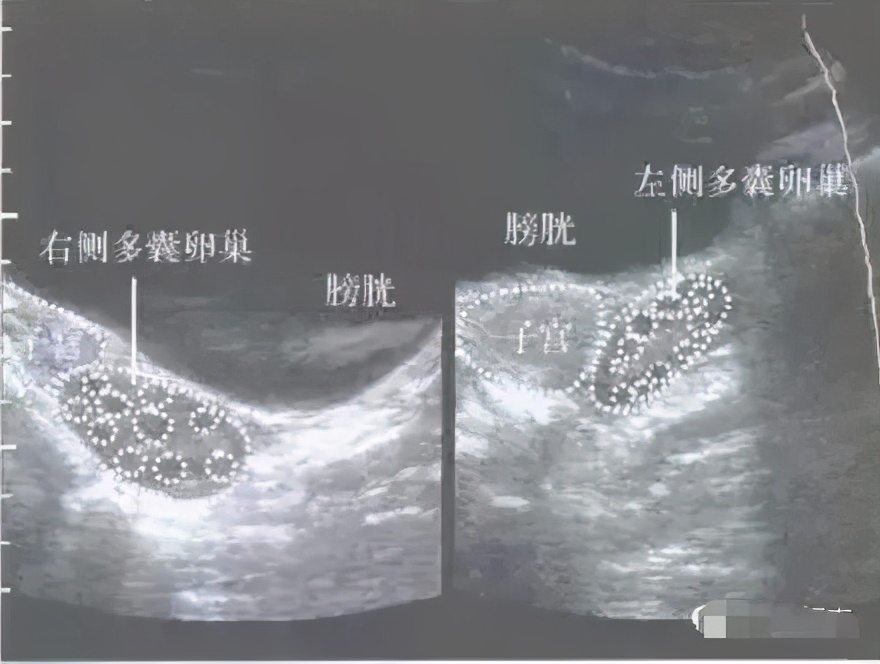

①B超检查提示双侧卵巢上小卵泡分别≥12个;

卵巢多囊样,英文缩写是PCO,和多囊卵巢综合征PCOS 少了一个字母,但这意思可大有不同。卵巢多囊样PCO是一种超声下观察到的状态,有比较多的小卵泡,可以是单侧,也可以是双侧。